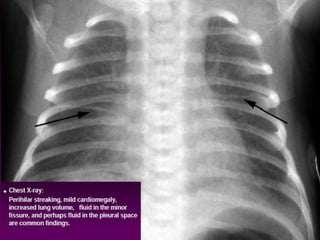

CXR   

Management Most significant discriminatoryfindings are the onset of the illness and the degree of distress exhibited by the infant Symptoms can last from a few hours to two days TTN is a clinical diagnosis CXR   